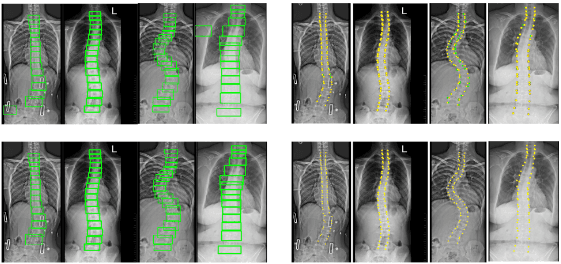

Automatic Spine Curvature Estimation from X-ray Images

Medical Image Analysis | Computer Vision | Deep Learning | Clinical Decision SupportARRTAC